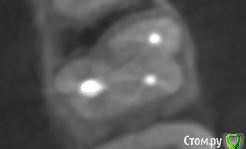

dmitrib81 Опубликовано 20 февраля, 2020 Автор Поделиться Опубликовано 20 февраля, 2020 еще фото Ссылка на комментарий

krokomot Опубликовано 19 февраля, 2020 Поделиться Опубликовано 19 февраля, 2020 в медиальном корне недопломбировка и наличие вероятно 4ого канала. Ссылка на комментарий

dmitrib81 Опубликовано 20 февраля, 2020 Автор Поделиться Опубликовано 20 февраля, 2020 Зуб делали много лет назад. Примерно неделю назад появились периодические боли, бывает целый день не болит, потом снова ноющая боль. С приёмом пищи никак не связано. На горячие и холод реакции нетПодскажите, может ещё прислать фоток из КТ Пикассо, а то я в этом ничего не понимаю, просто разных фото экрана прислал, без какого-либо понимания, на что смотреть.. Ссылка на комментарий